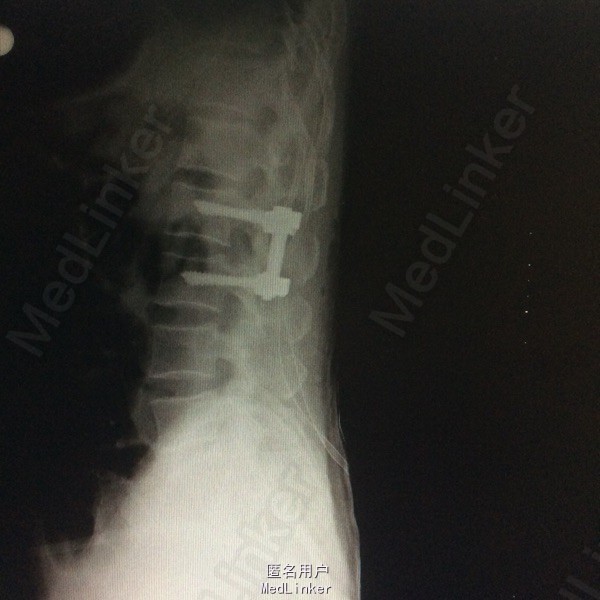

患者双下肢无明显浅感觉减退,肌力V级,肌张力不高,二便控制满意,病理征阴性。 腰椎核磁:腰1-4椎体右侧右肾下方团块状占位,大小约8#⃣6.8Cm,等T1长T2信号 腰椎Ct:占位周围见弧形钙化灶

腰椎神经鞘瘤 切除右侧横突,见腰2神经根延伸呈膜状,沿腰2神经跟出口将神经切断,完整取出肿物。